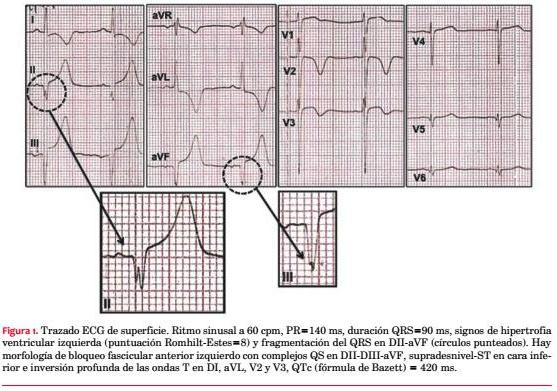

Paciente de sexo masculino, 21 años, sedentario, fumador intenso, exconsumidor de cocaína. No relata cifras elevadas de presión arterial (PA). Como antecedentes familiares destacaba la noción de padre, tío y hermano portadores de MCH, motivo por el cual concurre a control cardiológico ambulatorio. No presentaba antecedentes de MS en la familia. Mientras deambulaba presentó un episodio de pérdida brusca y transitoria de conocimiento, de escasos minutos, con recuperación ad integrum, precedido de dolor precordial. Hasta entonces el paciente manifestaba episodios ocasionales de palpitaciones rápidas, breves, en reposo. Examen clínico en la emergencia: paciente lúcido, eupneico, buen estado nutricional, con hematoma palpebral izquierdo. Al examen cardiovascular central no se palpaba el latido apexiano, ritmo regular de 60 cpm, S1 y S2 de tonalidad normal, soplo en mesocardio de intensidad II/VI (Levine) sin irradiaciones, que no se modificaba con la maniobra de Vasalva. Al examen vascular periférico, PA: 125/80 mmHg, pulsos simétricos normales, ausencia de ingurgitación yugular. Los campos pulmonares estaban libres y el examen neurológico era normal. El ECG basal de 12 derivaciones mostraba ritmo sinusal y marcadas alteraciones en la depolarización y repolarización ventricular (figura 1). La curva de biomarcadores de lesión miocárdica (TnI) fue negativa y el resto de la analítica de laboratorio fue normal.

Reportamos el caso de un joven con MCH asimétrica anteroseptal que se presentó con síncope y marcadas alteraciones en el ECG, entre las que destaca la fragmentación del complejo QRS, un hallazgo asociado a la presencia de fibrosis miocárdica de potencial valor pronóstico. Estratificamos precozmente el riesgo de MS como moderado, con base en las recomendaciones internacionales y el MHC RISK-SCD SCORE. En este contexto clínico, decidimos proceder al implante de un DAI como medida de prevención primaria razonable. Aun disponiendo de modernas técnicas de imagen y nuevos scores de riesgo confiables al lado del paciente, el perfil evolutivo impredecible de la MCH a menudo dificulta la toma de decisiones terapéuticas.